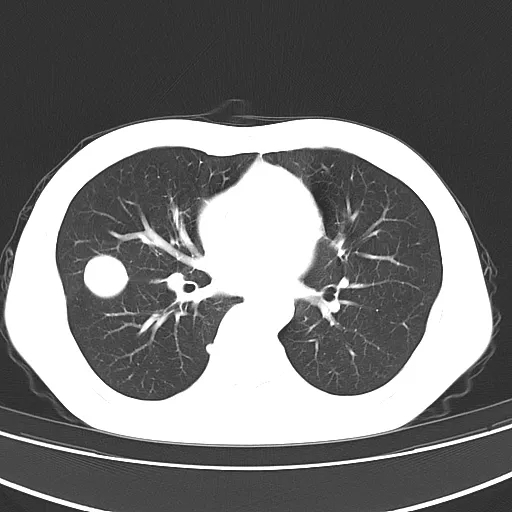

同时有气体和血液者称为混合型;

f020f06cec1226161c6ffadf6d4a7a55.jpg

创伤性假性肺囊肿多分布在肺野外周,可以伴骨折、肺挫伤、液气胸及纵隔、皮下气肿同时出现,囊肿内壁均匀、光滑,边缘多有斑片状渗出呈磨玻璃影或实变影改变,边界不清;短期内复查囊肿内密度容易变化,可以出现 3 种类型囊肿相互之间转化,但以空腔型转化为气液型囊肿或囊肿型转化为气液型囊肿较为多见

诊断创伤性假性肺囊肿需要有明确的外伤史此疾病多处于肺挫伤附近或中心,病变不稳定,短时间内病灶大小、形态均有明显改变。